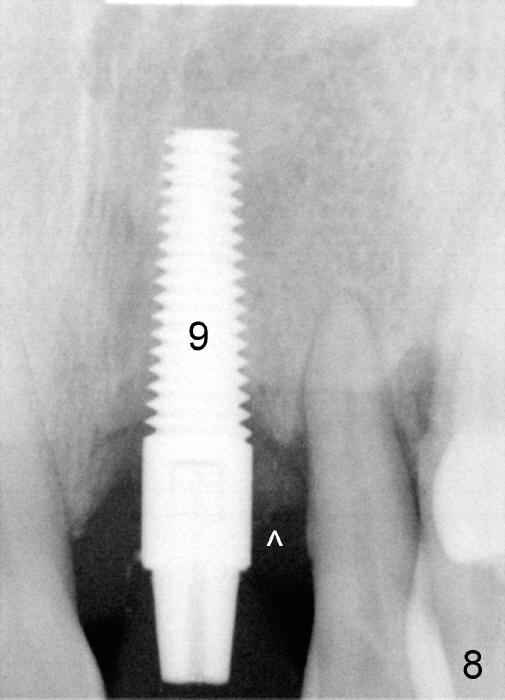

The most severely affected teeth (#6,7 and 9) are extracted and immediately replaced by 4x20 mm (#7) and 5x20 (#6,9) implants (Fig.4,5). Straight (0 degree) uniposts (3 and 4 mm, respectively) are rotated tightly into the wells of the implants by hand screw driver. In order to have reversibility to hybrid denture in the future, these uniposts are not cemented. Heavy retention grooves are placed between the uniposts and implants. Provisionals are fabricated immediately and cemented temporarily. To increase stability, flowable composite is added to the area between the provisionals of #6 and 7.

The provisional of #9 is still wiggling a little bit buccolingually. It is probably due to loose connection between the implant and the abutment, although follow up PAs do not support it (Fig.7,8; ^: bone graft at the time of immediate implants).